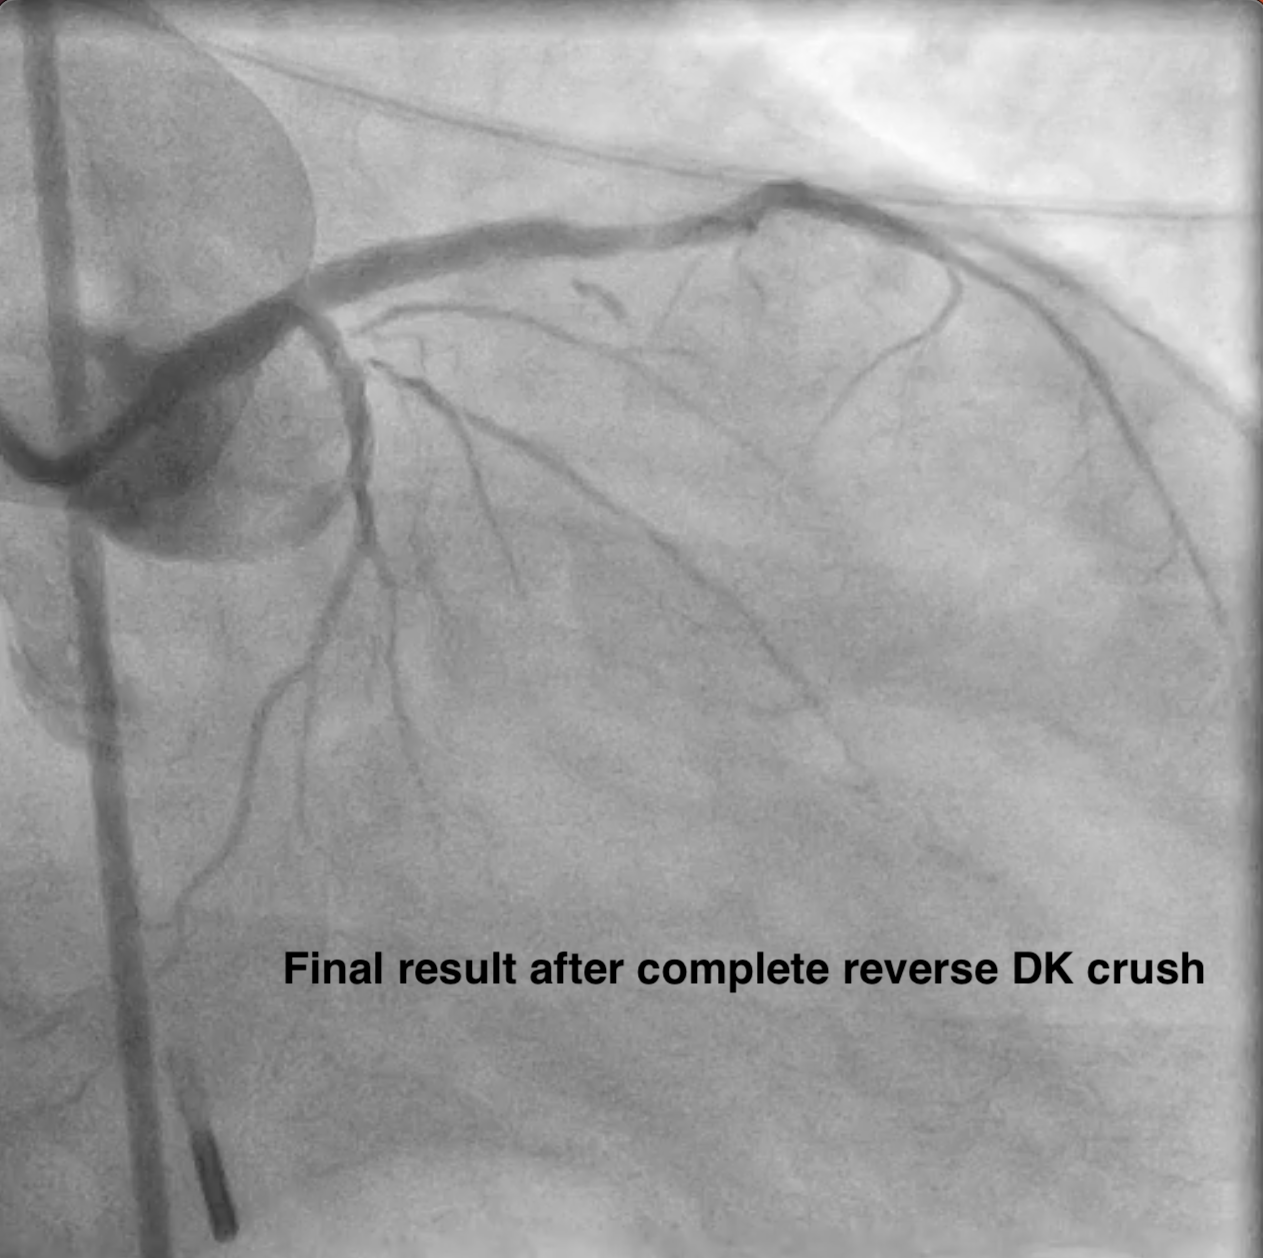

Access site: RRA 6F sheath, EBU 3.5 6F guiding catheter. IABP was inserted via RFA for hemodynamic support. A BMW guidewire (GW) was advanced into the LAD, & thrombus was aspirated. A Sion GW was then placed in LCX. IVUS guided a provisional strategy from LM to LAD restoring flow quickly. The lesion was pre-dilated with a 2.0 ¡¿ 20 mm balloon & a 2.5 ¡¿ 10 mm scoring balloon. Biomatrix Alpha stents (3.5 ¡¿ 36 mm & 2.5 ¡¿ 24 mm) were deployed from the LM to mid LAD & post-dilated. The LCX became jailed, so the T-and-Protrusion technique was initiated as a bailout, & a Biomatrix Alpha 2.5 ¡¿ 19 mm stent was positioned for TAP. After TAP, acute thrombosis developed at the neocarina of the LM. The patient received adequate heparin, intracoronary eptifibatide, & vasopressors. The procedure was stopped after achieving TIMI 3 flow in LAD & resolution of ST elevation. The patient was transferred to the ICU for intensive antithrombotic therapy. 3 days later, a relook angiogram via the LFA (EBU 3.5 7F) showed total LCX occlusion. IVUS confirmed excessive LCX stent protrusion into LM. Reverse Double Kissing Crush was performed. The protruded LCX stent was crushed with a 4.0 ¡¿ 12 mm non-compliant balloon, Sion Blue GW was advanced through the proximal strut, & final kissing inflation with proximal optimization was completed. Plaque protrusion at proximal LAD stent was corrected with prolonged NC balloon dilation. Final IVUS & angiography showed good result.

¡ß In high-risk left main bifurcation intervention during STEMI, a provisional stenting strategy may fail when the side branch is significantly compromised. ¡ß Urgent bailout techniques, though rapid, carry a risk of acute thrombosis, particularly in thrombus-rich lesions. ¡ß Conversion to a dedicated bifurcation technique (reverse Double Kissing Crush) offers better scaffolding and predictable side-branch access when provisional and TAP strategies fail. ¡ß Adequate and intensive antithrombotic therapy is essential in thrombotic left main bifurcation lesions before performing definitive stenting.